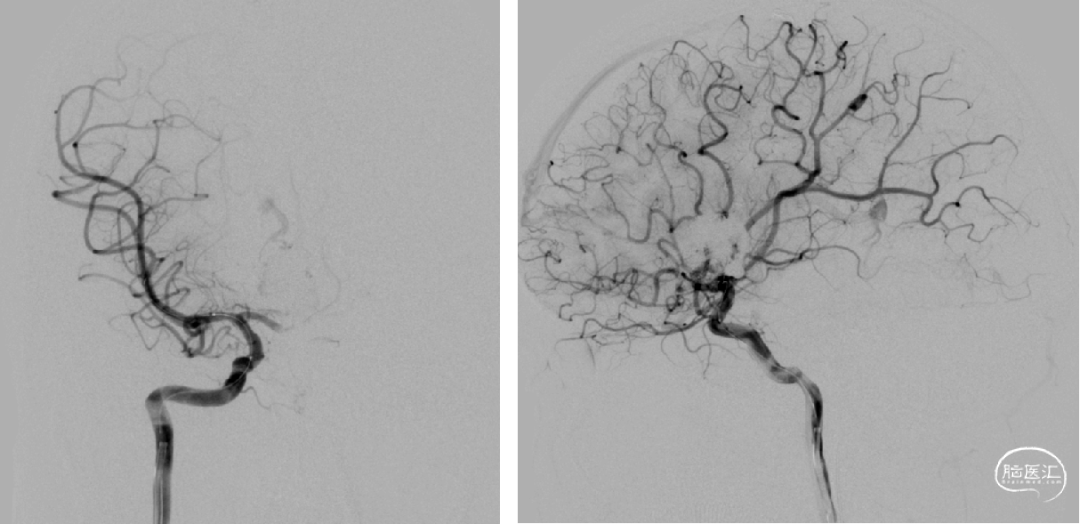

术后造影脑动静脉畸形消失

术后即刻造影